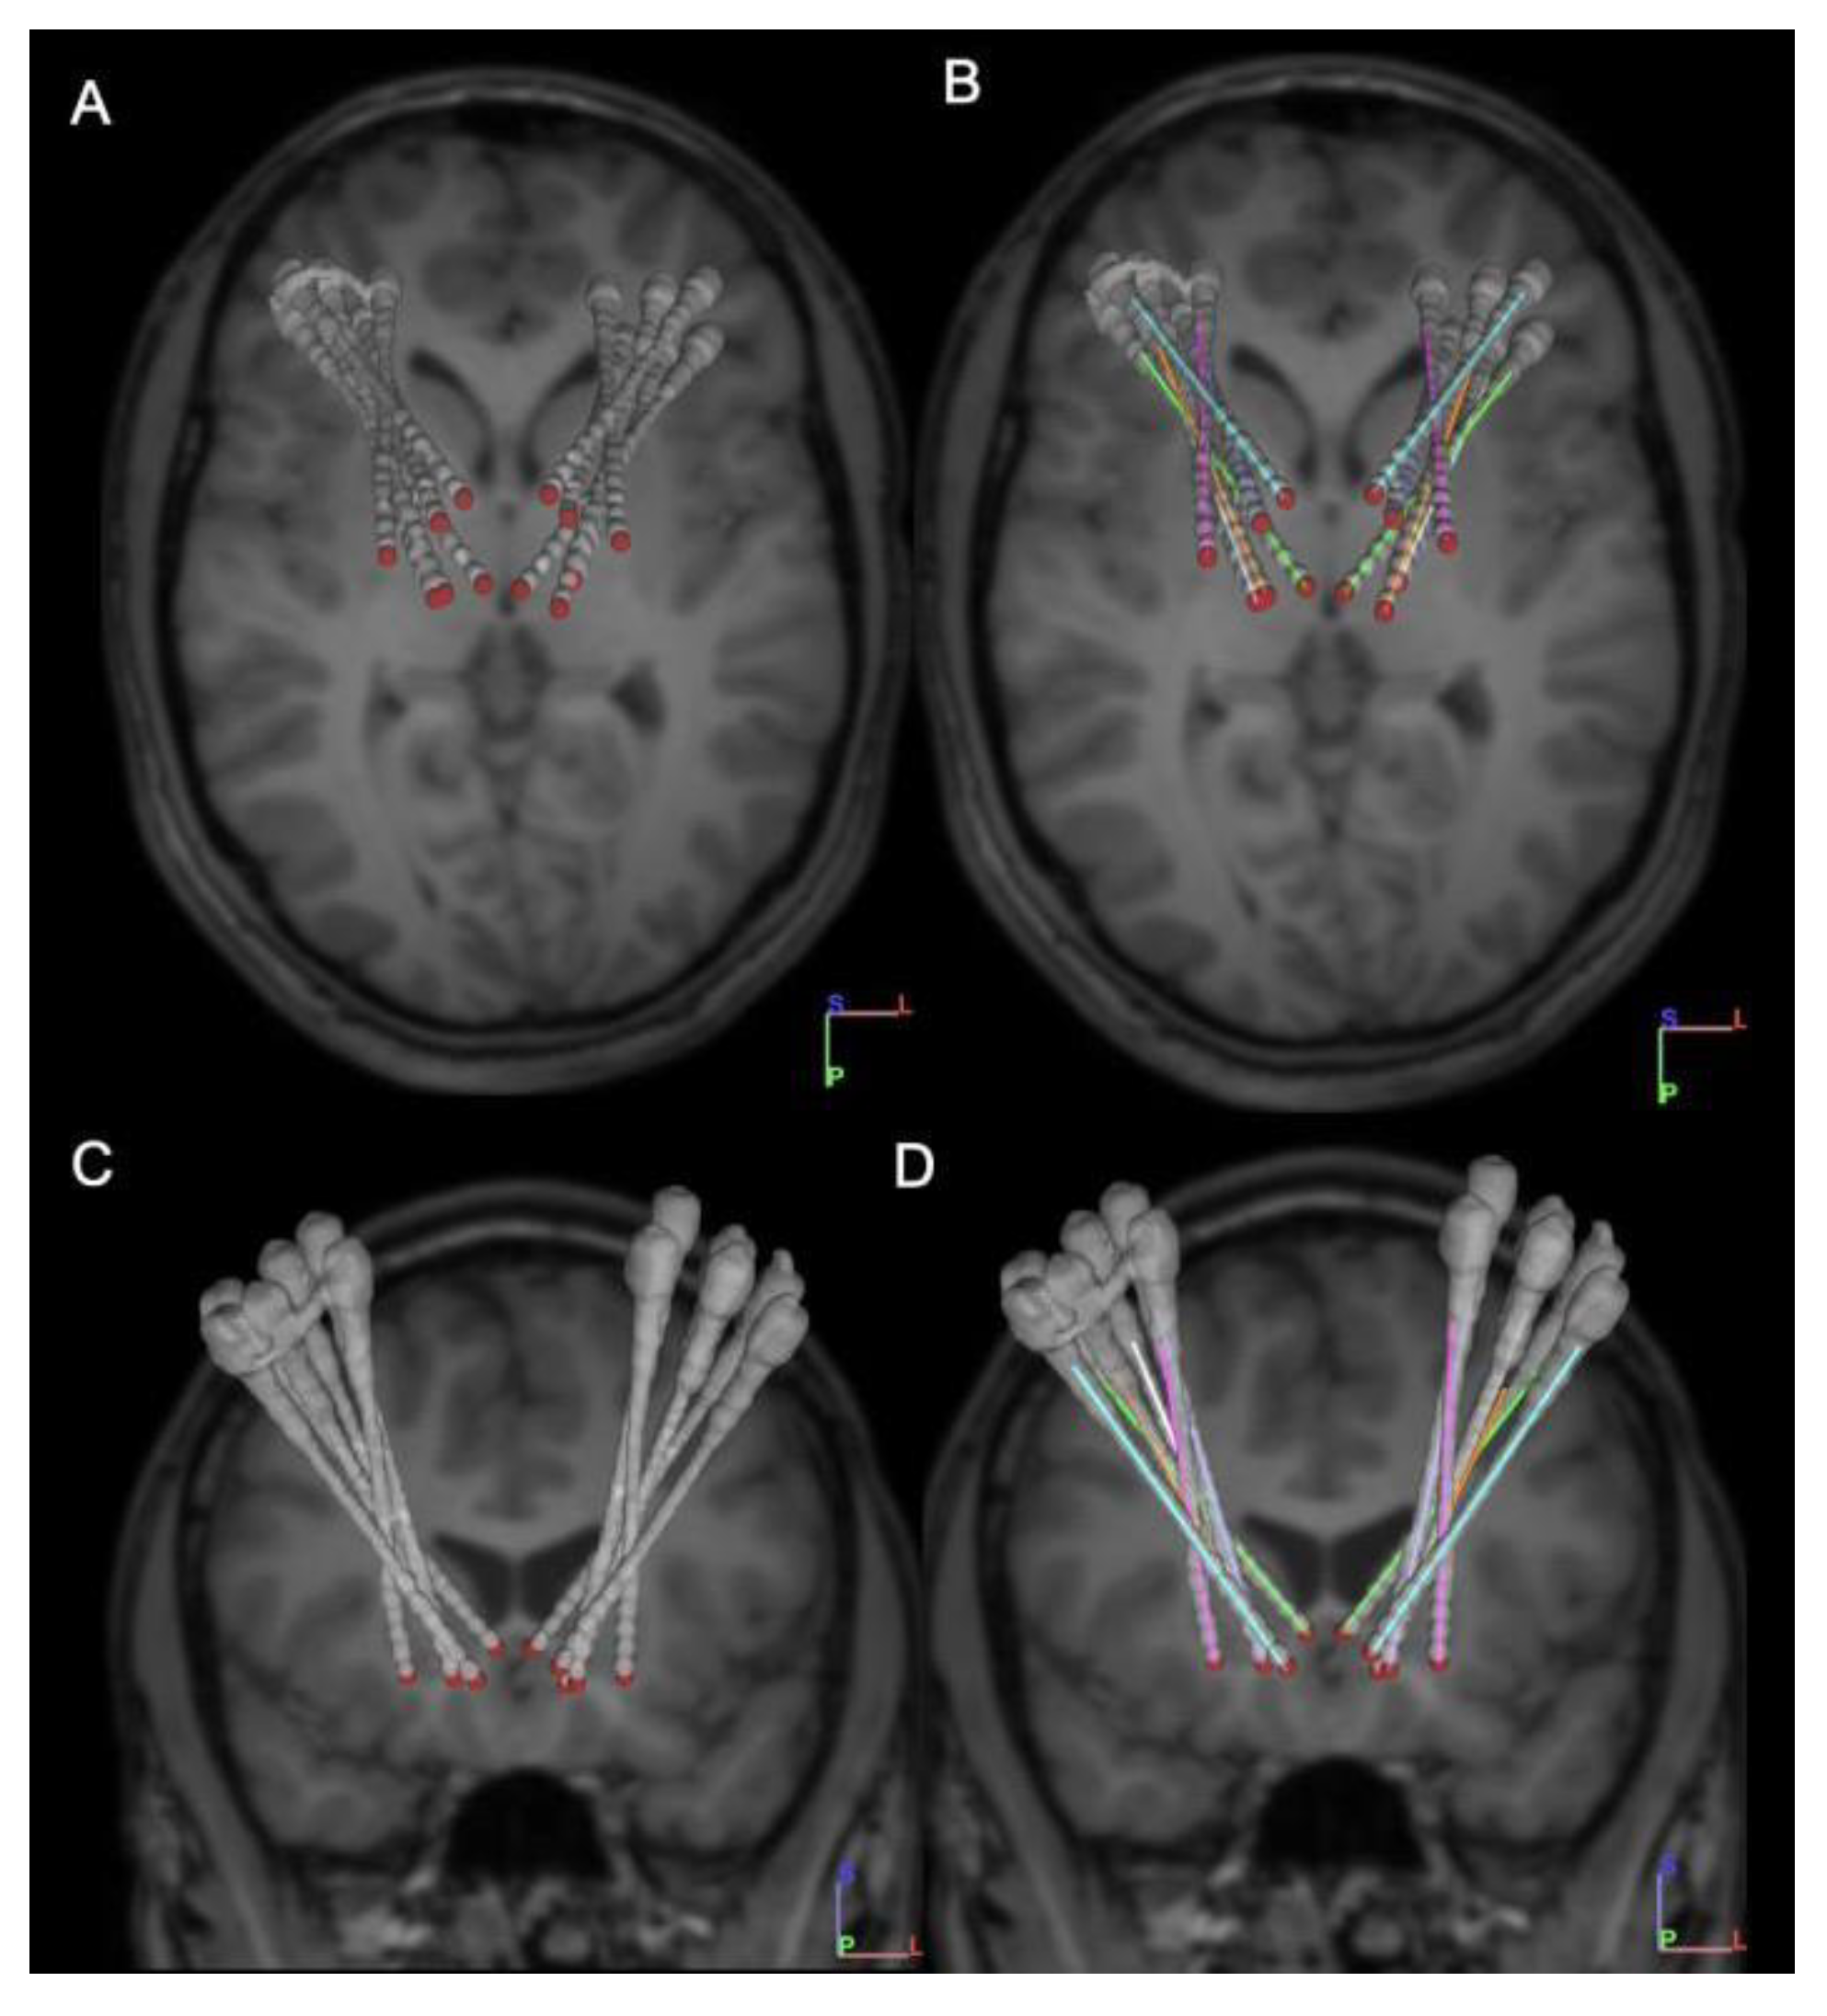

| AC-PC Coordinates | ||

|---|---|---|

| Target | Left | Right |

| Vo STN | Lat: −13.5 | Lat: 13.5 |

| AP: −2.0 | AP: −2.0 | |

| Vert: 1.0 | Vert: 1.0 | |

| GPi Posterior | Lat: −21.5 | Lat: 21.5 |

| AP: 4.0 | AP: 4.0 | |

| Vert: −3.0 | Vert: −3.0 | |

| Gpi Anterior | Lat: −12.0 | Lat: 12.0 |

| AP: 9.0 | AP: 9.0 | |

| CM Parafasciular nucleus | Lat: −5.0 | Lat: 5.0 |

| AP: −4.0 | AP: −4.0 | |

| Vert: 0.0 | Vert: 0.0 | |

| VIM Thalamus | Lat: −14.0 | Lat: 14.0 |

| AP: −5.0 | AP: −5.0 | |

| NA | Lat: −9.3 | Lat: 9.0 |

| AP: 13.93 | AP: 14.68 | |

| Vert: −0.87 | Vert: −1.44 | |